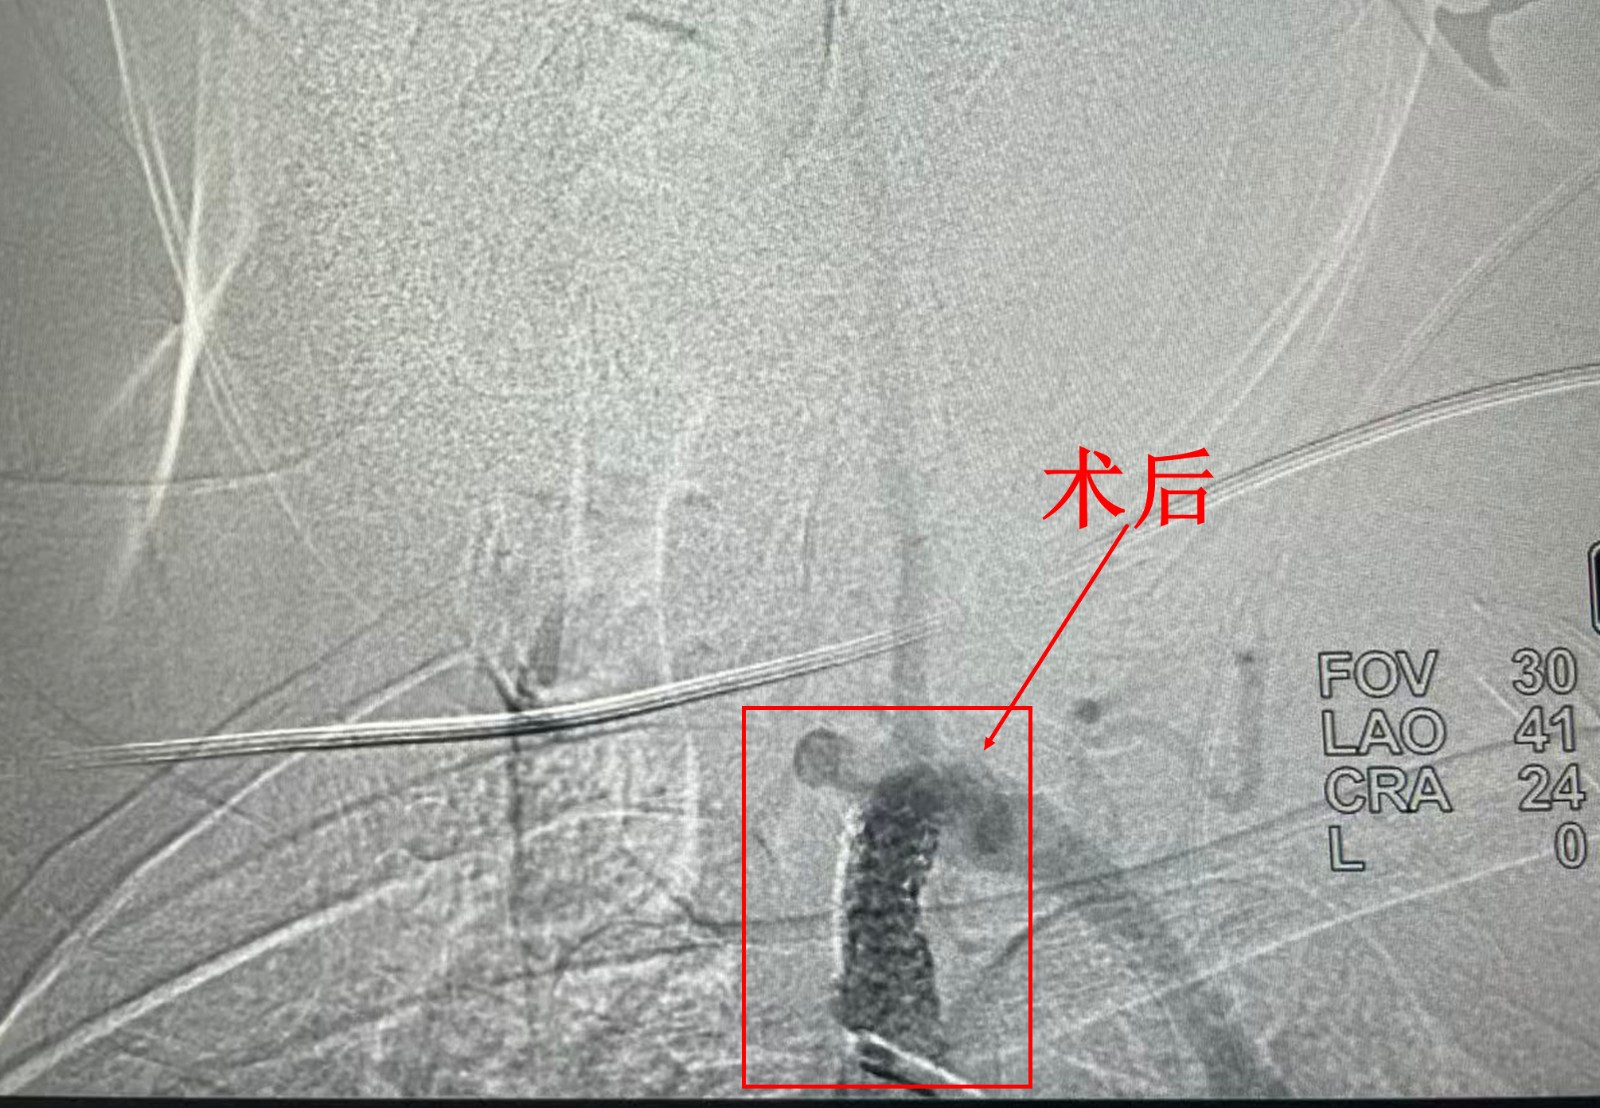

8月29日,在完善各项术前准备后,叶伟团队为患者实施微创介入手术。通过穿刺股动脉,将导管精准送达病变部位,先行球囊扩张狭窄段,再成功植入血管支架。术后造影显示,原本狭窄的血管恢复通畅,“盗血”现象立即消失。

“左手终于暖和了,脉搏也跳动了!”术后次日,欧某成就感受到明显改善。他激动地表示:“从去年心梗到这次晕厥,都是县中医医院救了我。没想到在家门口就能得到这么好的治疗!”